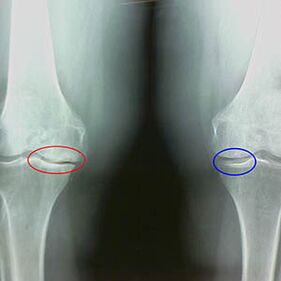

Early X -Ray characteristics of the second stage of knee arthrosis:

- the sharpened edges of the tibia's intercity tubercles, where the cross ligament is attached;

- narrowing of the joint precipice from the medial side;

- The evaluated edges of the bone bones from the medial side, less often in the lateral ones - depending on the development of the deformity of the valgus or the version of the joints.

For the second stage in LarsenNarrowing the gap of joints with more than 50% is characteristic, but this can only be checked in dynamics or comparison with different joints.